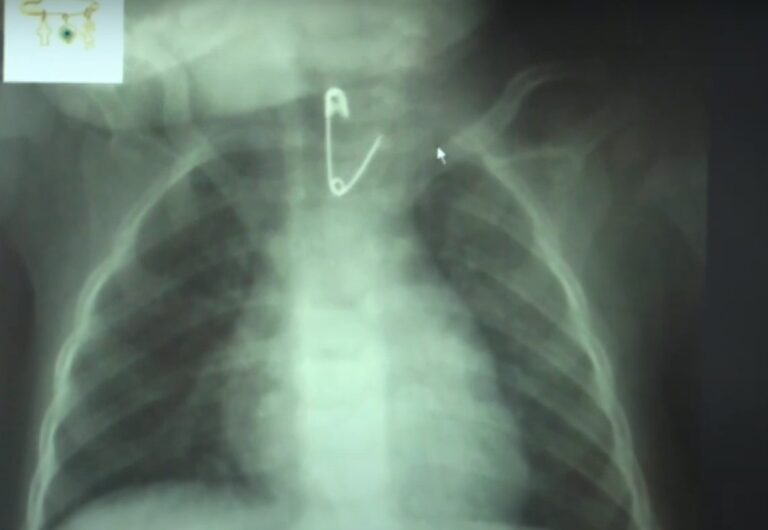

Δεν είναι όμως το μοναδικό περιστατικό. Οι γιατροί της ΩΡΛ κλινικής του Ιπποκράτειου Νοσοκομείου Θεσσαλονίκης πρόσφατα κλήθηκαν να αντιμετωπίσουν και άλλα παρόμοια περιστατικά. Όπως αυτό με εννέα μηνών βρέφος που κατάπιε παραμάνα. Σε άλλες περιπτώσεις παιδάκι κατάπιε μεταλλικό κουμπί από ρούχο ενώ ένα άλλο σκουλαρίκι. Οι επιστήμονες συμβουλεύουν τους γονείς να είναι ιδιαίτερα προσεκτικοί.